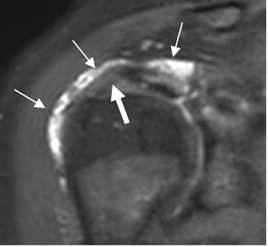

Fig 93. Pinzamiento interno anterior.

RM coronal en STIR. Líquido en la bursa SASD (Flechas delgadas), con hiperintensidad del tendón supraespinoso por tendinitis, pero sin ruptura completa. (Flecha gruesa).